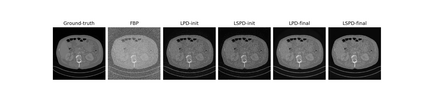

We propose a new type of efficient deep-unrolling networks for solving imaging inverse problems. Conventional deep-unrolling methods require full forward operator and its adjoint across each layer, and hence can be significantly more expensive computationally as compared with other end-to-end methods that are based on post-processing of model-based reconstructions, especially for 3D image reconstruction tasks. We develop a stochastic (ordered-subsets) variant of the classical learned primal-dual (LPD), which is a state-of-the-art unrolling network for tomographic image reconstruction. The proposed learned stochastic primal-dual (LSPD) network only uses subsets of the forward and adjoint operators and offers considerable computational efficiency. We provide theoretical analysis of a special case of our LSPD framework, suggesting that it has the potential to achieve image reconstruction quality competitive with the full-batch LPD while requiring only a fraction of the computation. The numerical results for two different X-ray computed tomography (CT) imaging tasks (namely, low-dose and sparse-view CT) corroborate this theoretical finding, demonstrating the promise of LSPD networks for large-scale imaging problems.